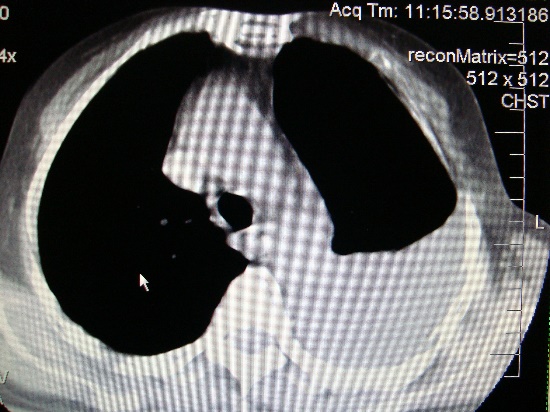

Каким патологическим субстратом обусловлен данный патологический процесс// +воздухом в плевральной полости// жидкостью в плевральной полости// инфильтрацией легочной ткани// полостью распада// спаечным процессом в плевральной полости

С чем связан механизм развития данного патологического процесса// со спонтанным разрывом легкого// с растеканием жидкости в плевральной полости// с инфильтрацией легочной ткани// с распадом легочной ткани// +со спаечным процессом в плевральной полости